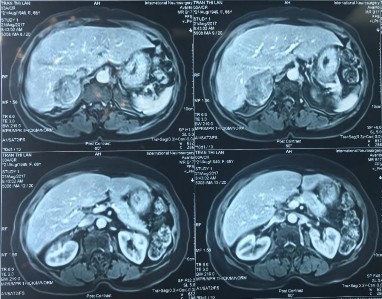

Phim MRI bướu tuyến thượng thận 2 bên

Bệnh phẩm bướu sắc bào tủy TTT bên trái

Phim MRI sau phẫu thuật cắt bướu TTT bên trái

[Nguyễn P., 37 tuổi, SNV: 214061952]